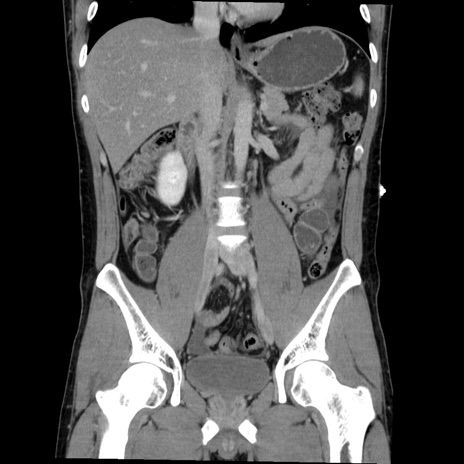

症例36(冠状断像)

【症例】20歳代 男性

【主訴】心窩部痛

【現病歴】今朝より上腹部痛あり。一旦軽快していたが再度出現したため救急要請。昨日夕に白身の魚を含む刺身を食べた。

【身体所見】BP 136/89mmHg、HR 74/min、BT 37.0℃、腹部:膨満、軟、心窩部に圧痛あり。反跳痛なし、筋性防御なし、腸雑音やや亢進あり。

【データ】WBC 17700、CRP 0.48